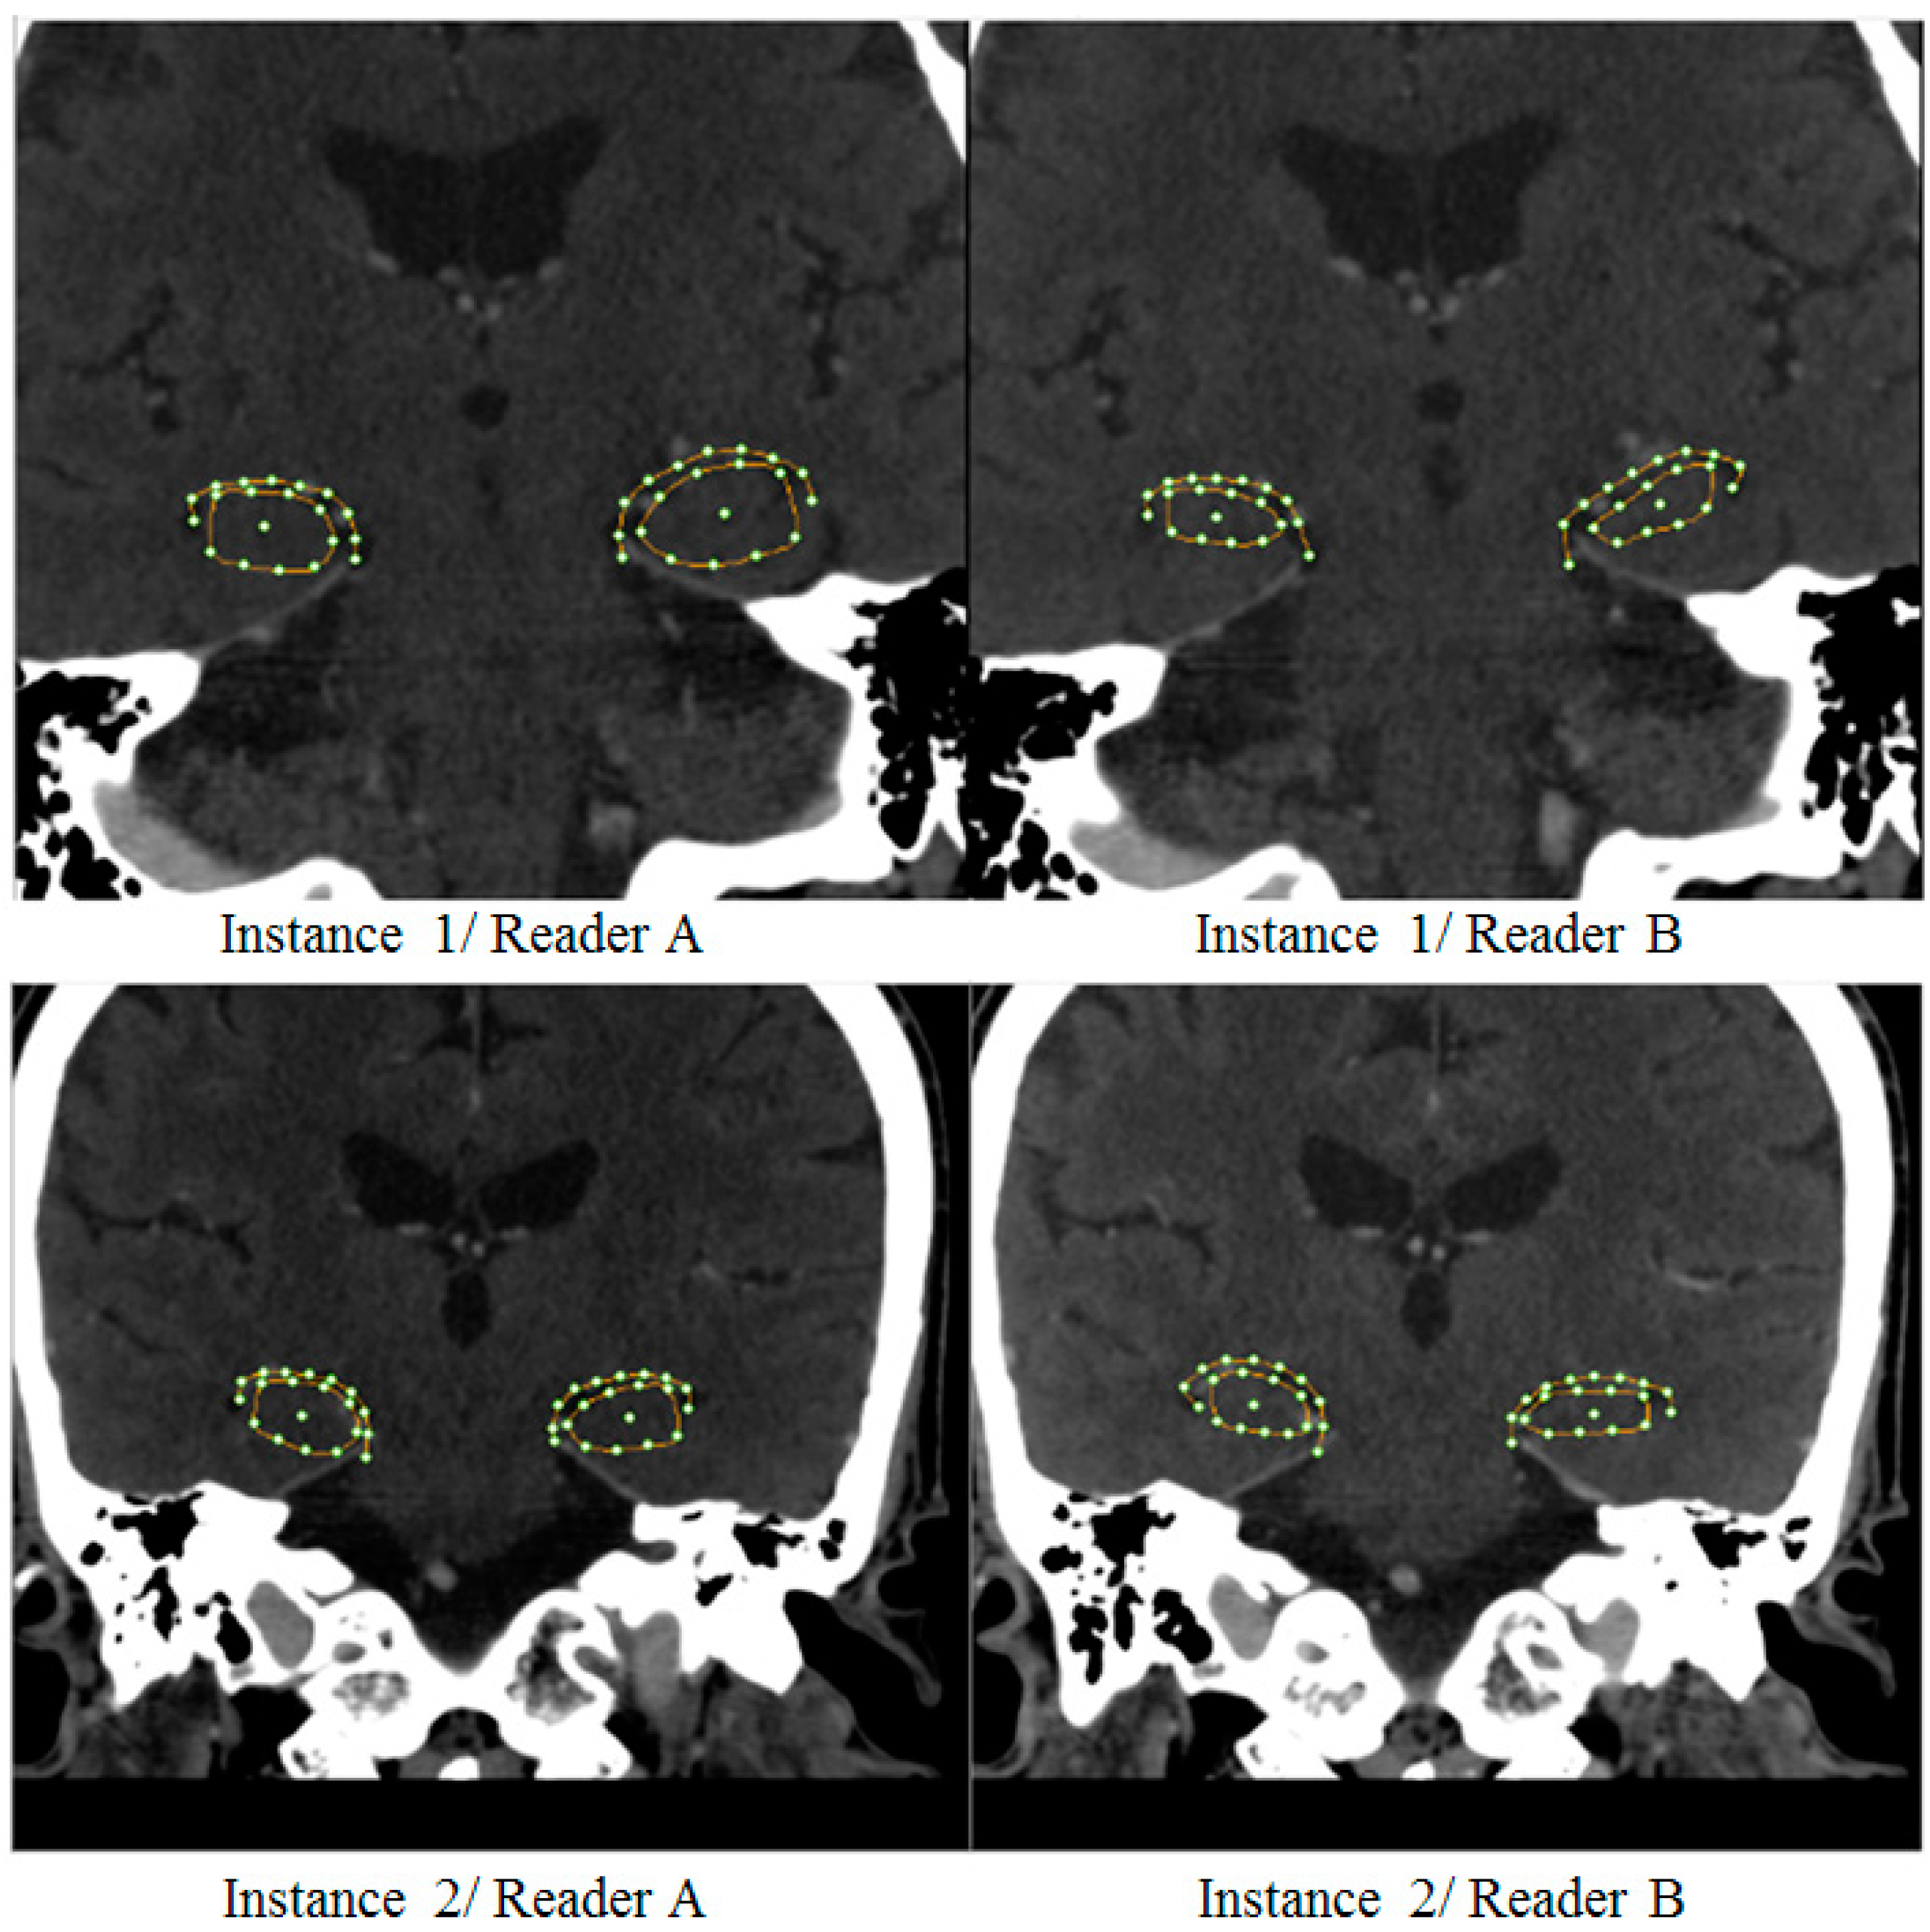

2.3. SSA Software

3.1. Hippocampal Morphology Variability